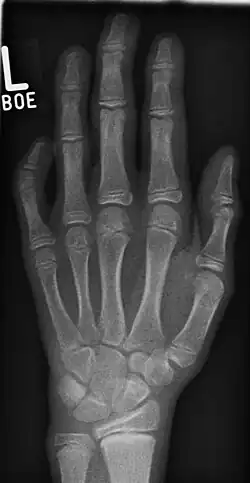

Unter Klinodaktylie versteht man allgemein die in der Regel angeborene seitlich-winklige Abknickung eines Fingerglieds im Handskelett. Man unterscheidet die

- Klinoteledaktylie: Abwinklung im Endgelenk (Distales Interphalangealgelenk)

- Klinomesodaktylie: Abwinklung im Mittelgelenk (Proximales Interphalangealgelenk)

- Klinobasodaktylie: Abwinklung im Grundgelenk (Metacarpophalangealgelenk)